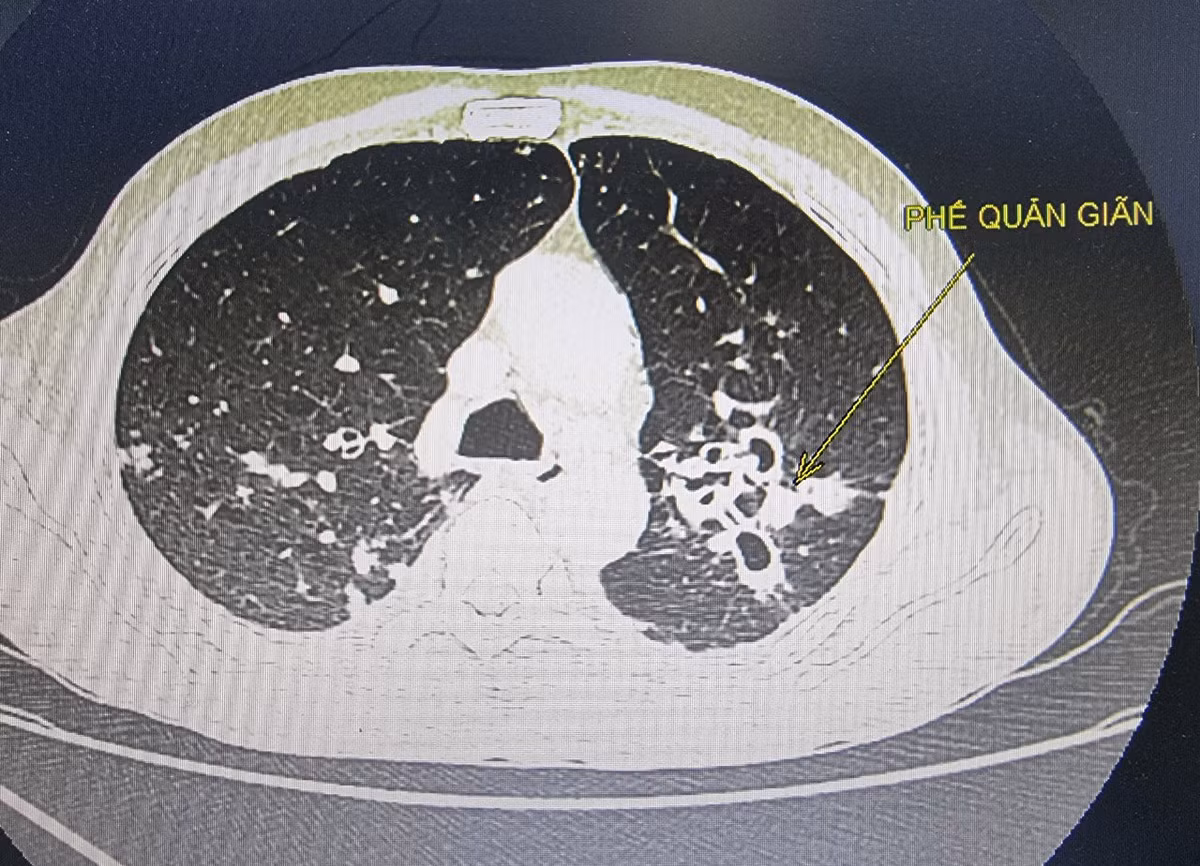

Rất hiếm khi ho dai dẳng, kéo dài lại là dấu hiệu cảnh báo ung thư, thường các dấu hiệu này là do chảy dịch sau mũi, hen suyễn, trào ngược thực quản, nhiễm trùng... Nhưng nếu sau khi được điều trị mà bệnh không thuyên giảm hoặc ho ra máu, nhất là khi bạn không phải là người hút thuốc lá thì nên đến gặp bác sĩ, có thể bạn sẽ được cấy đờm hoặc làm các xét nghiệm, chụp chiếu… cận lâm sàng để rà soát ung thư phổi.